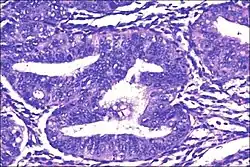

| Micrograph showing simple endometrial hyperplasia, where the gland-to-stroma ratio is preserved but the glands have an irregular shape and/or are dilated. Endometrial biopsy. H&E stain. | |

- Endometrial hyperplasia (simple or complex) - Irregularity and cystic expansion of glands (simple) or crowding and budding of glands (complex) without worrisome changes in the appearance of individual gland cells. In one study, 1.6% of patients diagnosed with these abnormalities eventually developed endometrial cancer.[7]